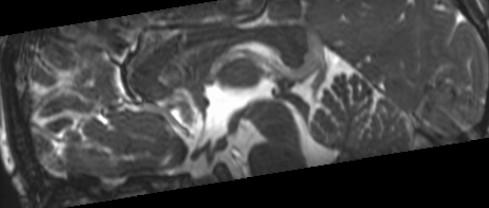

Note the CSF flow dephasing through the defect in the floor of the third ventricle.